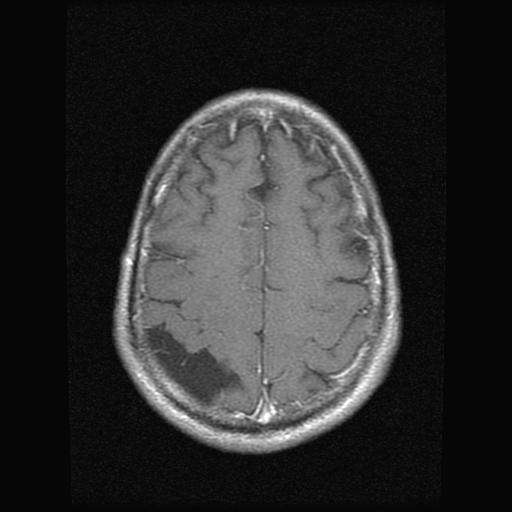

From this back view we can see the asymmetry in the top left (actual right side). The other dark areas in middle region of brain are part of normal CSF circulation system.

Another view looking down. Dark area is CSF (salt water). Blood has contrast dye in it, so bone and blood vessels show up white, low density regions indicate darker.